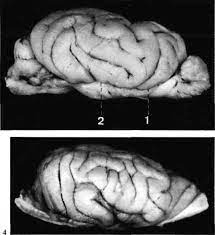

otter brains